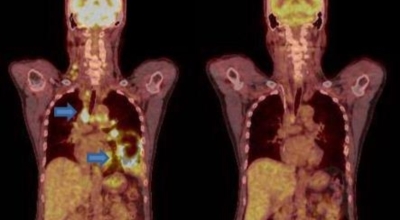

폐암 검사는 X-ray를 통해서 검사하는데 , 크기가 작거나 구석에 위치한 경우 확인이 어려운 경우도 있답니다. 그리고 조직 검사를 통해서 정확한 진단을 하게 돼요. 폐암이 발견되면 종양의 크기나 전이 여부 , 위치에 따라서 수술 여부를 결정하게 돼요.